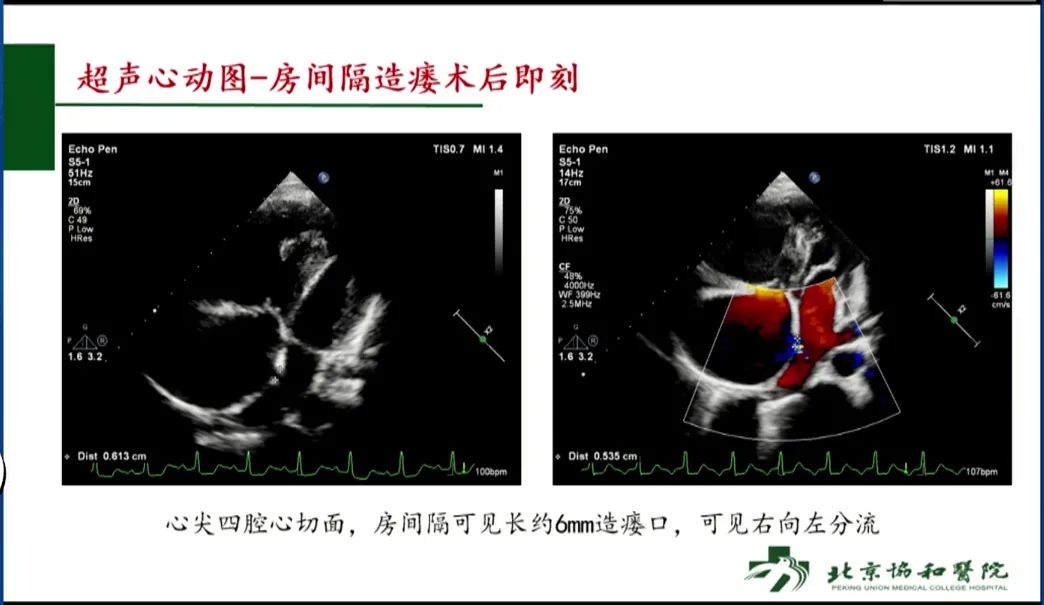

BAS术后即刻超声心动图检查可见6mm造瘘口,呈右向左分流。术后48小时左右,患者开始恢复对利尿剂和多巴胺的敏感性,24小时出入量由正转负并维持负平衡,全身水肿逐渐消退。患者胸闷气短症状和低氧血症也得以缓解,解除呼吸机辅助后,逐步改为储氧面罩和鼻导管吸氧,最终摆脱对氧气的依赖。